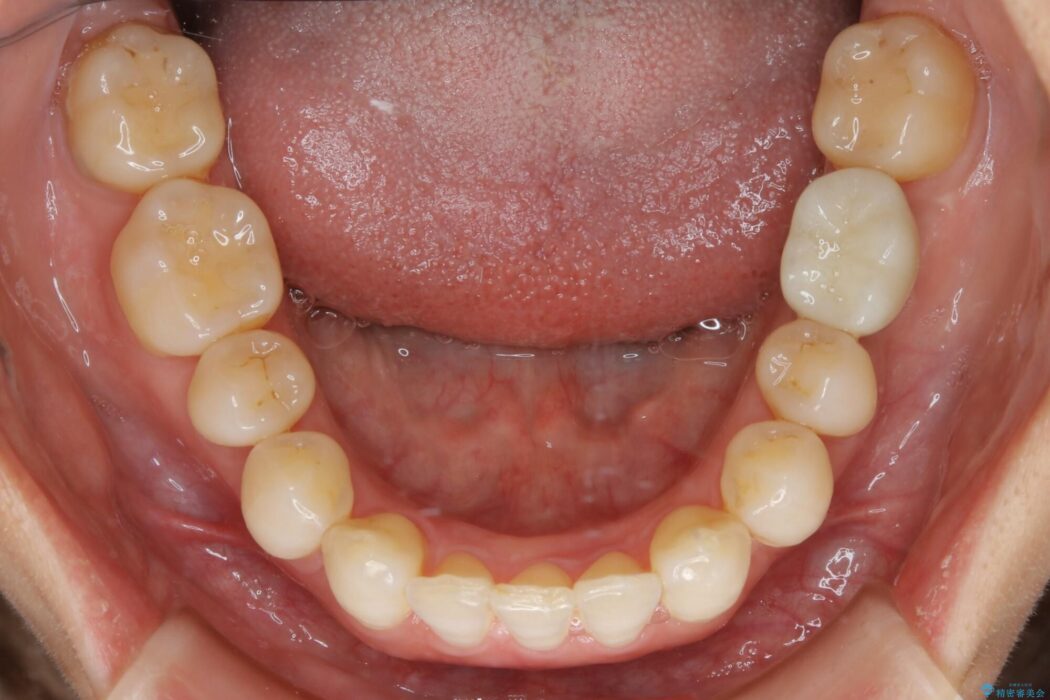

治療計画を立てる上で詳しく精密検査をしたところ、左下の6番目の歯につきまして治療が必要な状態であることが分かり、かぶせ物を外し、内部を確認しました。

結果としては深い部分で根が破折してしまっていました。